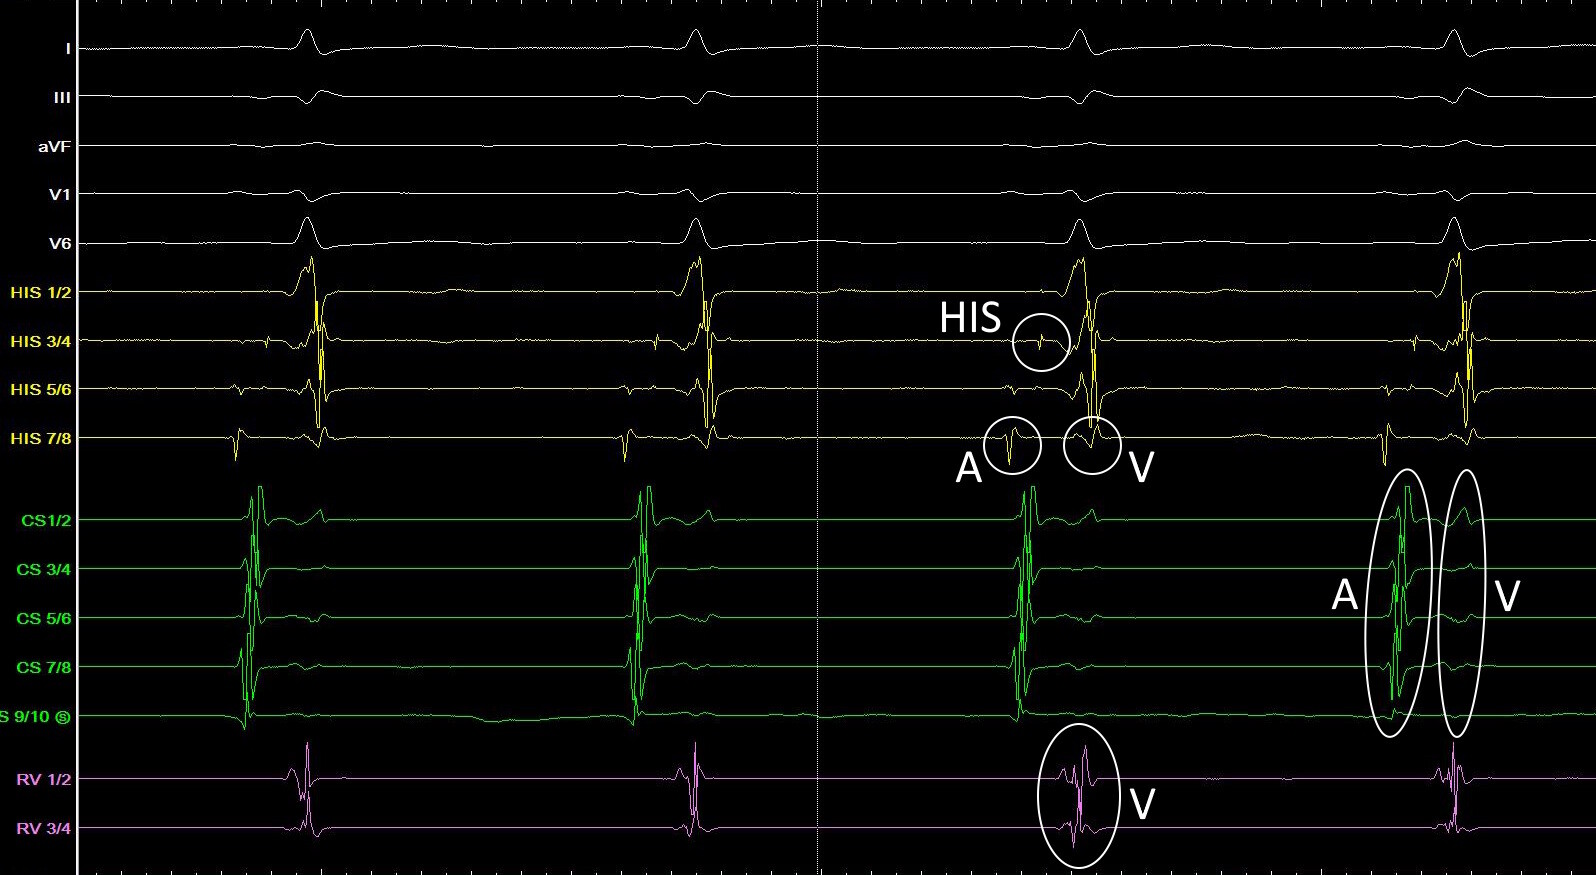

Abbildung 2 zeigt Beispiele für typische intrakardiale Signale.

Intrakardiale Signale der Katheter während eines unauffälligen Sinusrhythmus.

Abbildung 2: Intrakardiale Signale der Katheter aus Abbildung 1 während eines unauffälligen Sinusrhythmus. Je nach Lage des Katheters lassen sich auf diesem nur ventrikuläre (V) Signale (RV-Katheter), ventrikuläre und atriale (A) Signale (CS-Katheter) oder ventrikuläre und atriale Signale sowie das charakteristische scharfe HIS-Elektrogramm (HIS-Katheter) ableiten.